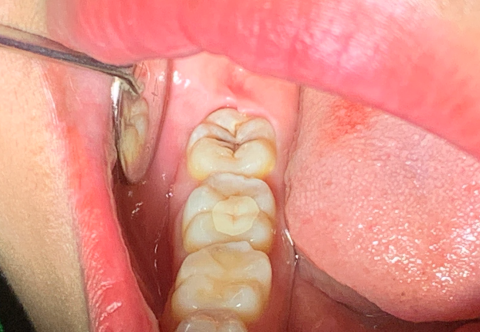

Giá chụp thép răng sữa ảnh 3

Chi phí chụp thép răng sữa tùy thuộc vào chất liệu, lợi ích và chế độ bảo hành đi kèm. Giá chụp răng thép cho bé sẽ dao động từ khoảng 600.000 - 2.500.000 rất phù hợp với chi phí của phụ huynh. Bởi chất liệu khá phổ biến ngoài xã hội và quá trình chế tác đơn giản nên nên bố mẹ có thể yên tâm về chụp thép răng sữa cho con.

4. Quy trình chụp thép răng sữa cho trẻ

Làm việc đúng quy trình sẽ giúp cả y bác sĩ lẫn khách hàng thấy được rõ phương án xử lý, các bước thực hiện và kết quả theo từng giai đoạn. Việc chụp thép bảo vệ răng sữa cho con rất quan trọng nên y bác sỹ sẽ áp dụng đúng quy trình và tuân thủ theo tiêu chuẩn của bộ Y Tế.

- Bước 1: Các y bác sĩ sẽ tiến hành thăm khám tổng quát cho các bé, đánh giá phim X - quang do bệnh nhân mang đến rồi mới lên phương án xử lý. Sau khi xác định rõ các vấn đề thì bác sĩ sẽ tư vấn cụ thể thời gian hoàn thành cũng như chi phí thực hiện dịch vụ.

- Bước 2: Thăm khám và vệ sinh răng miệng miễn phí trước khi thực hiện chụp thép răng, sẽ được vệ sinh răng miệng bao gồm lấy cao răng, làm sạch khoang miệng, loại bỏ tình trạng viêm lợi.

- Bước 3: Tiến hanh thu nhỏ răng một chút để vừa lắp.

- Bước 4: Lấy dấu răng của trẻ và lựa chọn size chụp thép phù hợp, vừa với thân răng và khít với 2 răng kế cạnh.

- Bước 5: Tiến hành lắp theo tiêu chuẩn và quy trình.

- Bước 6: Bác sĩ loại bỏ hoàn toàn chất gắn dư thừa, chỉnh khớp cắn và hướng dẫn cách chăm sóc, vệ sinh tại nhà.

- Bước 7: Các bé cần đến nha khoa tái khám định kỳ từ 3-6 tháng một lần để vệ sinh răng miệng cũng như lấy cao răng. Định kỳ sẽ có đội ngũ chăm sóc khách hàng của Yota gọi điện nhắc nhở đặt lịch mình đi thăm khám để bảo vệ hàm răng của các bé.